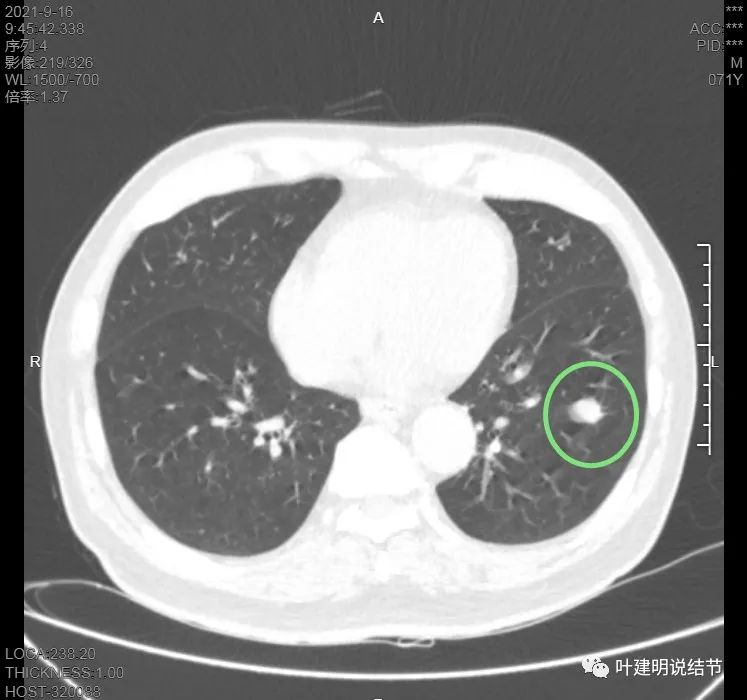

肿瘤筛查指标中的CEA与CA724高于正常。我们先来看其左下叶病灶的CT图像:

上图示病灶在左下叶,红色所指的与绿色箭头所指的是两个病灶,不相连的,实性结节

上图也示病灶是两个的,小的与大的之间有间隙的。大的病灶呈长方形似的

上图见主病灶长方形,边缘平直且光滑,没有毛刺、分叶或胸膜牵拉,粉色箭头示小病灶,在主病灶边上